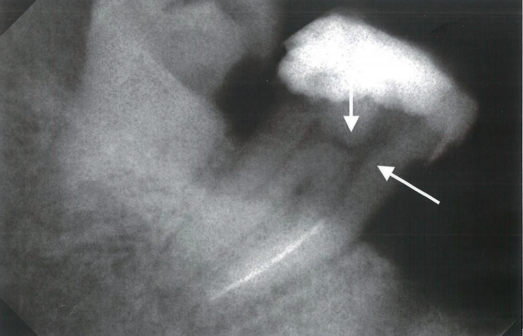

根管马达怎么修根管内器械分离的影响因素_https://www.jmylbn.com_新闻资讯_第2张

1  过小开髓孔导致的下颌磨牙近中根管中器械分离。可见髓室顶(短箭头)和未充分磨除的根管口牙本质三角(长箭头),这些都妨碍了根管冠1/3处直线通路的建立